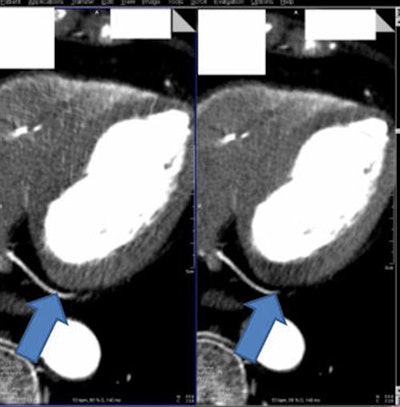

Among the more than 750 myocardial regions assessed, they found the regions prone to beam hardening were readable and diagnostic with use of the beam-hardening correction kernel versus images processed using a standard kernel (D30f).

When the algorithm was employed, the group found significantly lower overall mean myocardial attenuation than without it. Relative differences from average myocardial attenuation were also smaller with use of the algorithm (p < 0.01) (European Radiology, September 2016, Vol. 26:9, pp. 3,215-3,222.)

"Hypoattenuation in regions with beam-hardening artifact was consistently corrected towards reference mean myocardial attenuation with the D33f kernel, providing a more homogeneous attenuation of the myocardium," the authors wrote. "The implementation of this beam-hardening correction kernel may thus improve assessment of CT MPI datasets in patients."